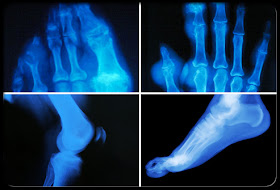

Gout (Gouty Arthritis) and Hyperuricemia

Gout is a form of arthritis. It is also called gouty arthritis. Gout can cause an attack of sudden burning pain, stiffness, and swelling in a joint. Over time, gout attacks can harm your joints, tendons, and other tissues.

The term gout refers the disease that is caused by an overload of uric acid in the body. Eventually, this leads to painful arthritic attacks.

Normally, uric acid in blood travels to the kidneys, where it passes out in urine. Gout occurs when uric acid builds in the body and forms crystals in the joints or in soft tissue.

The most common sign of gout is a nighttime attack of swelling, tenderness, redness, and sharp pain in the big toe. Gout attacks also appear in feet, ankles, knees, fingers, heels, and elbows.

Severe gout in the fingers results in large, hard deposits of crystals of uric acid. These deposits are called tophi.

Gouty arthritis is a painful condition that results from crystals of uric acid depositing in joint tissues, causing attacks of joint inflammation (arthritis).

Gouty arthritis is characterized by a rapid onset of pain in the affected joint followed by warmth, swelling, reddish discoloration, and marked tenderness.